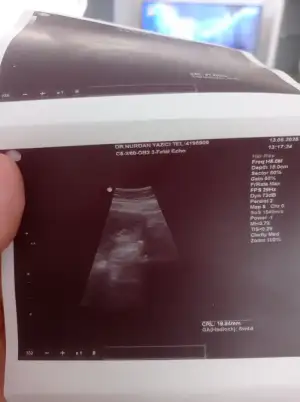

Ramzi teorisine göre tahmin yapalım

Bu kızımın 8 haftalık abdominal ultrason görüntüsü plasentası sağ da yani gerçekte sol da demekRamzi teorisi tutuyor

Bu kızımın 8 haftalık abdominal ultrason görüntüsü plasentası sağ da yani gerçekte sol da demekRamzi teorisi tutuyor

Bu kızımın 8 haftalık abdominal ultrason görüntüsü plasentası sağ da yani gerçekte sol da demekRamzi teorisi tutuyor

Bu kızımın 8 haftalık abdominal ultrason görüntüsü plasentası sağ da yani gerçekte sol da demekRamzi teorisi tutuyor

Bu kızımın 8 haftalık abdominal ultrason görüntüsü plasentası sağ da yani gerçekte sol da demekRamzi teorisi tutuyor

Plasenta neresi okuyor acabaBu kızımın 8 haftalık abdominal ultrason görüntüsü plasentası sağ da yani gerçekte sol da demekRamzi teorisi tutuyor

Bu erkek canım ramzi teorisine göre sola yerleşmiş plasenta sagda yani erkek teoriye göre

Doktor plasentasi solda demisti canim hatta o beyazlik olan yer dedi plasentasiBu erkek canım ramzi teorisine göre sola yerleşmiş plasenta sagda yani erkek teoriye göre